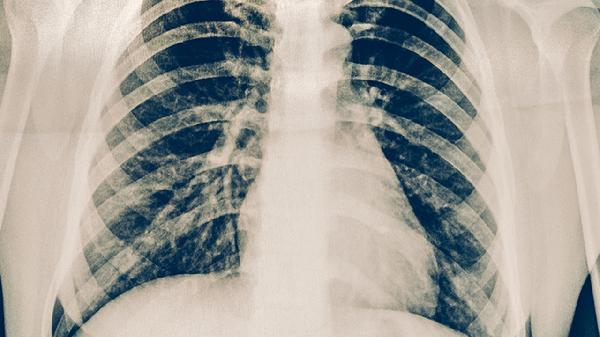

肺大泡破裂可通过卧床休息、氧疗、胸腔闭式引流、药物治疗、手术治疗等方式治疗。肺大泡破裂通常由剧烈运动、外伤、肺部感染、慢性阻塞性肺疾病、先天性肺发育不良等原因引起。